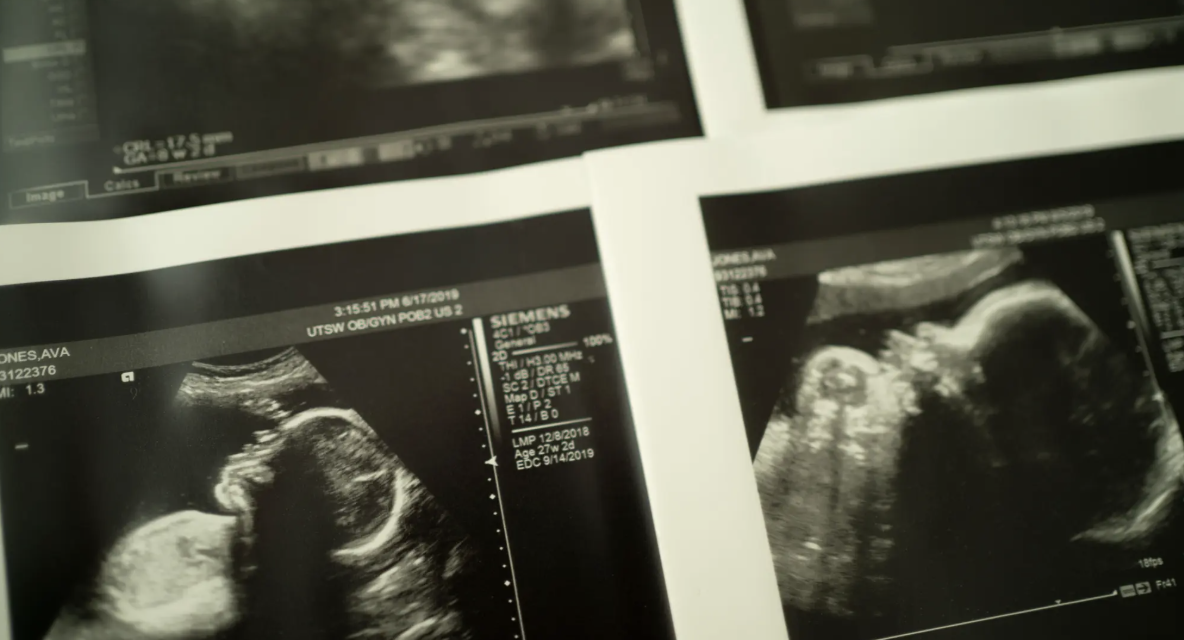

Ultrasound images of Giles Jones, who was stillborn to Ava Jones in 2019. Research shows that of the more than 20,000 stillbirths in the U.S. each year, as many as 25% may be prevented. (Photo: Nitashia Johnson, Special to ProPublica)

Four clinical sites and one data coordinating center spanning the country — California, Oregon, Utah, New York and North Carolina — will come together to form the consortium, each bringing its own expertise. Most will focus on ways to predict and prevent stillbirths, though they also plan to address bereavement and mental health after a loss. Research shows that of the more than 20,000 stillbirths in the U.S. each year, as many as 25% may be prevented. For deliveries at 37 weeks or more, that figure jumps to nearly half.